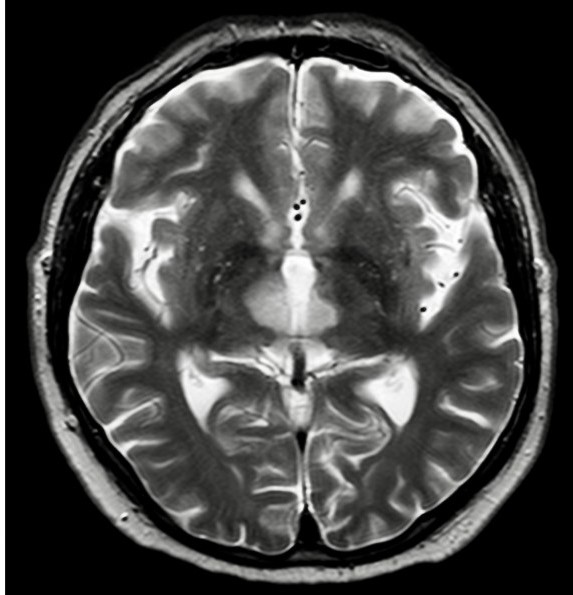

Okklusjon av Percherons arterie gir bilaterale infarkter i thalamus, hvilket er en uvanlig tilstand. Man klarer sjelden å påvise okklusjon av arterien ved bildediagnostikk, og diagnosen stilles indirekte ved funn av bilaterale infarkter i mediale thalamus med eller uten affeksjon av mesencephalon (2).

Vår pasient var en mann i slutten av 60-årene, som brått ble bevisstløs på ferie i utlandet. Han ble raskt hentet av ambulanse og kjørt til nærmeste sykehus. Det ble ikke gitt trombolytisk behandling fordi årsaken til bevissthetstapet var uklar. Ved ankomst ble han intubert og man bemerket at venstre pupill var større enn høyre. CT caput og CT angiografi tatt innleggelsesdagen var uten aktuelle patologiske funn. MR caput tatt dag 4 av sykehusoppholdet påviste infarkter bilateralt medialt i thalamus (bildet til høyre).